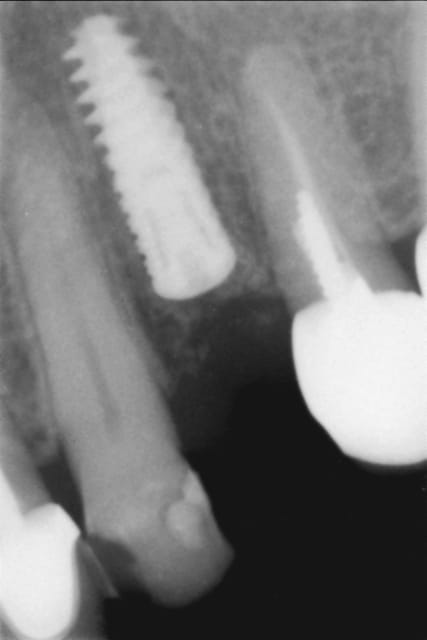

Un "vieux cas" LEONE qui se passe bien malgré des conditions de départ et de chirurgie pas au mieux! 4 ans déjà et aspect sympa très stable dans le temps. une de mes extractions implantation immédiate en site "pas idéal".La chronologie en rx.

Janvier 2008 vzunxr - Eugenol

Octobre 2008 ehmsfj - Eugenol

Mars 2008 jt5qx2 - Eugenol

Novembre 2011 ane4ar - Eugenol